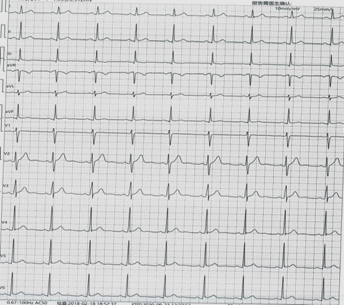

此心電圖診斷為

A.竇性心動過緩

B.大致正常心電圖

C.三度房室傳導(dǎo)阻滯

D.心房顫動

『正確答案』B